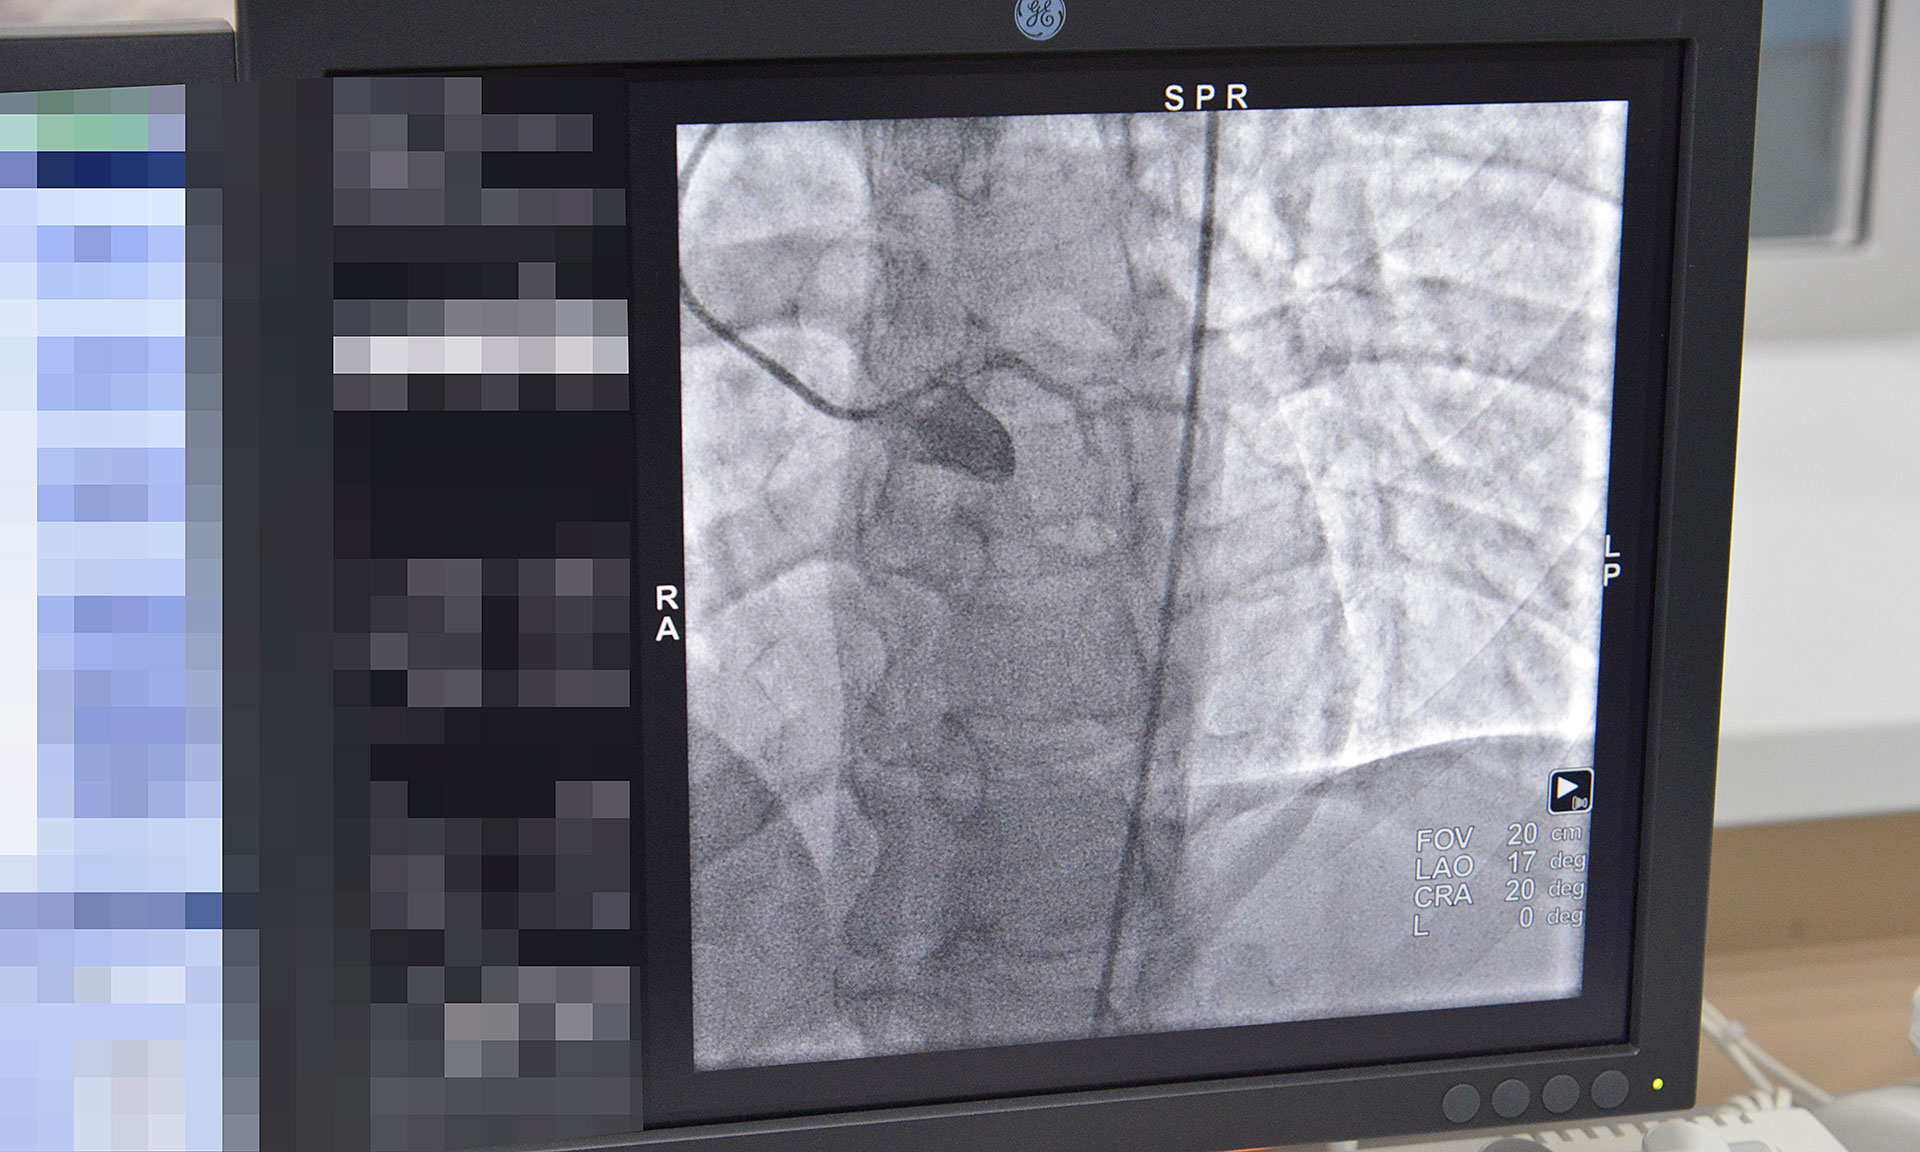

Главный врач Брянской городской больницы № 1 Константин Воронцов сообщил, что с февраля 2018 года в ГАУЗ «Брянская городская больница № 1» функционирует новое структурное отделение рентгенохирургических методов диагностики и лечения. Данное отделение открыто благодаря приобретению дорогостоящего оборудования -ангиографической установки «Инова» за счет денежных средств, выделенных областным бюджетом в сумме 37 млн. рублей. Это позволит открыть второй региональный центр для лечения больных с сердечно-сосудистой патологией, применяя высокотехнологические методы лечения, а именно: стентирование коронарных сосудов, сосудов нижних конечностей; оперативное лечение сосудистой патологии головного мозга.

В настоящее время в отделении проводится коронарография пациентам с сердечно-сосудистой патологией. В дальнейшем, при получении лицензии на проведение высокотехнологической медицинской помощи, будет проводиться стентирование сосудов.

В 2018 году запланировано проведение 300 коронарографий и 250 стентирований сосудов.